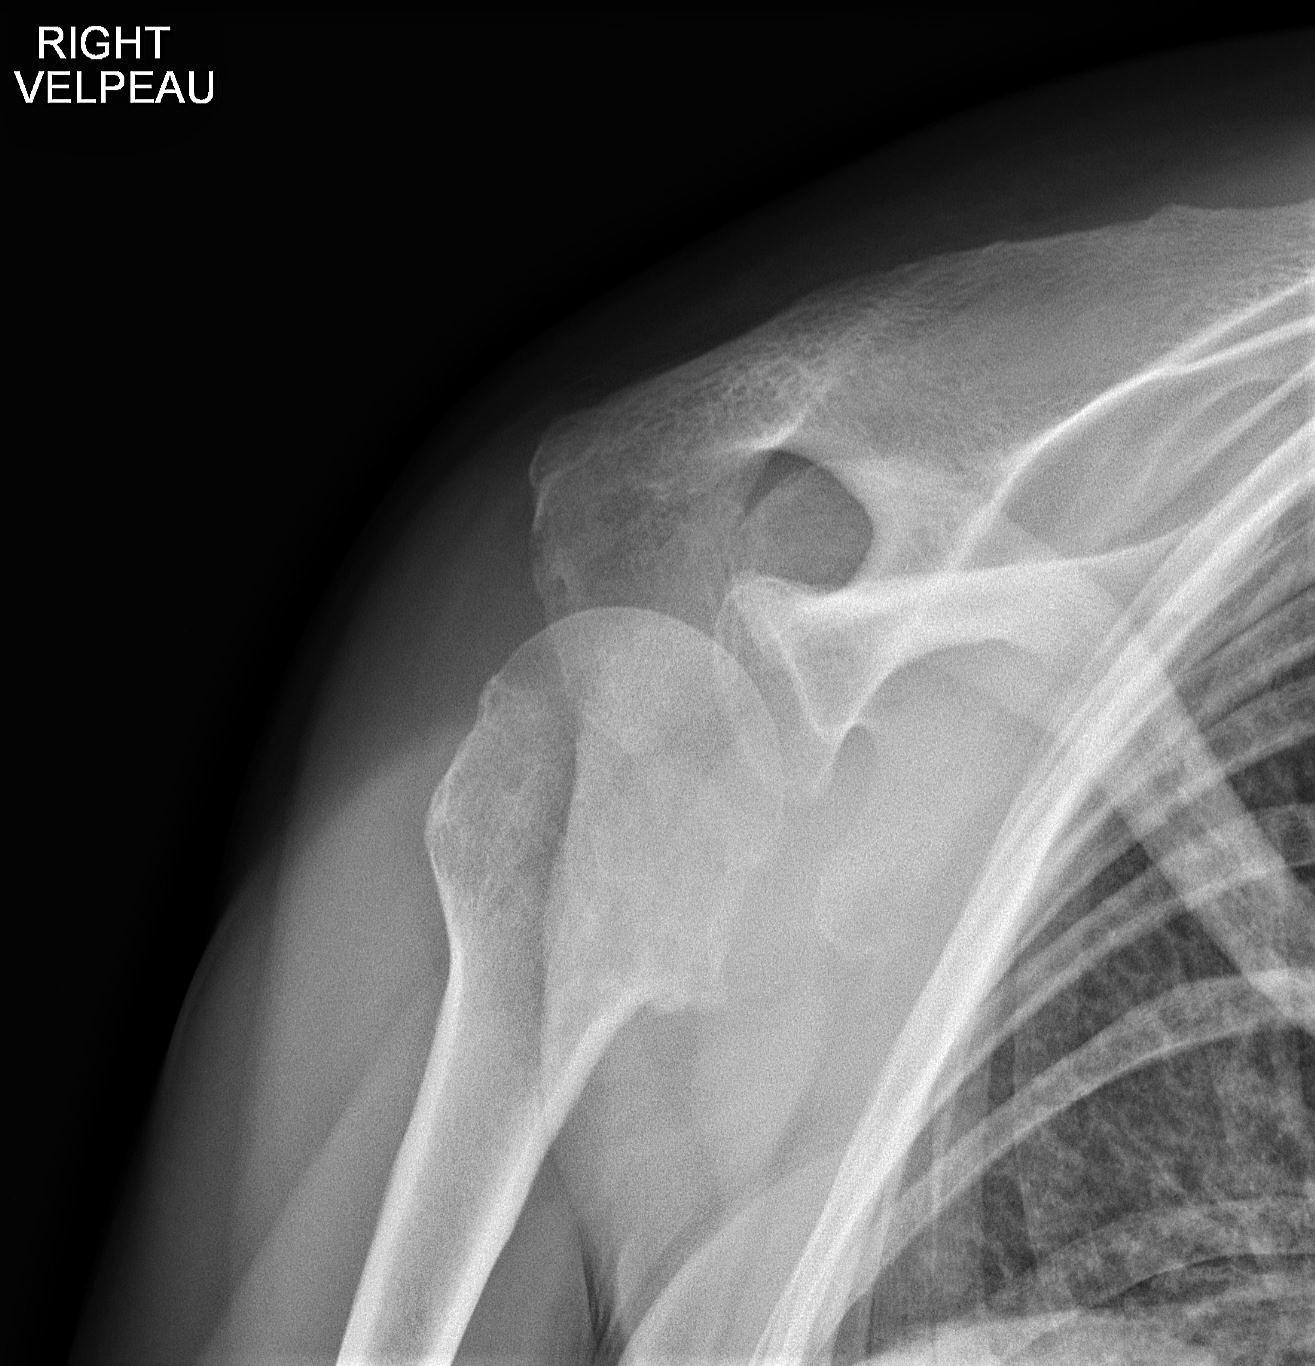

Andrew Murphy, Radiopaedia.org. From the case rID: 46646

Au moindre doute : cliché de Bloom et Obata (= profil axillaire traumatologique)

Aspect radiologique PIEGEUX:

- disparition de l’interligne articulaire (trop bel aspect sphérique de la tête humérale)

- cliniquement : rotation externe impossible (signe de l’aumône)